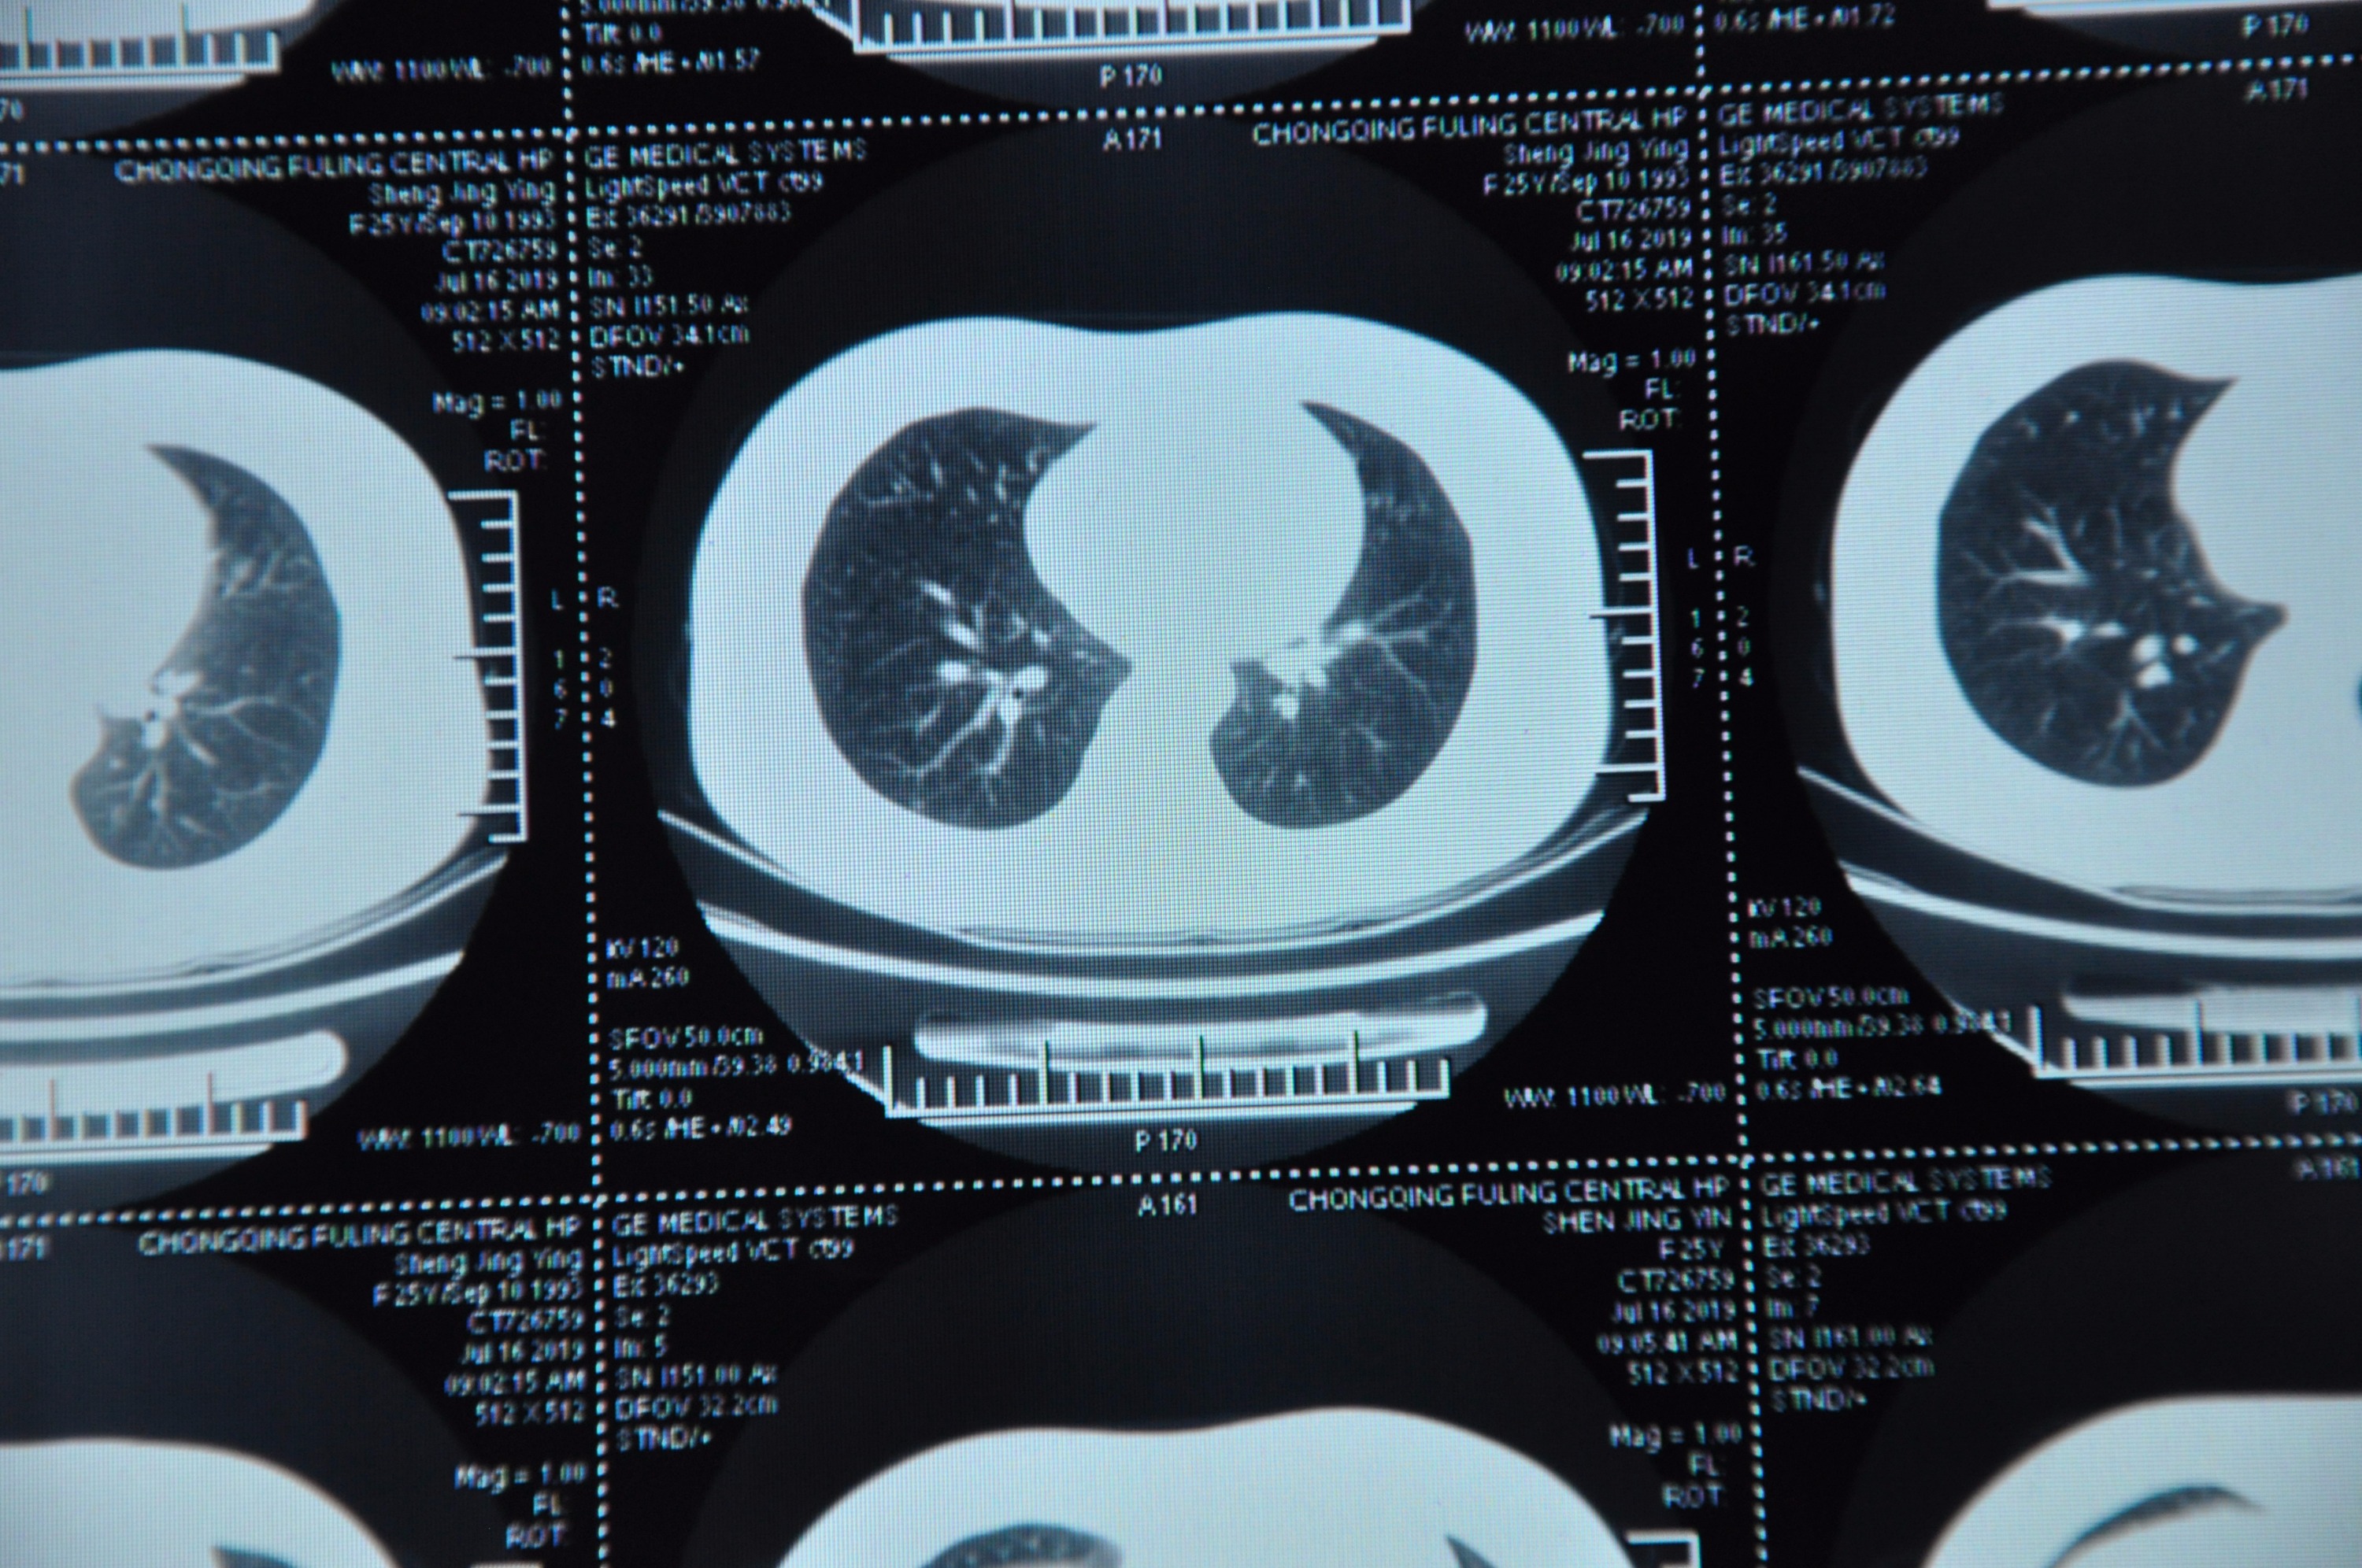

参加gwy入职体检检出来肺结节,请戴主任帮我看一下,是不是我得过结核,我现在有没有结核?还有现在能判断良性恶性吗?怕体检被刷下来

不知道能不能看得清楚